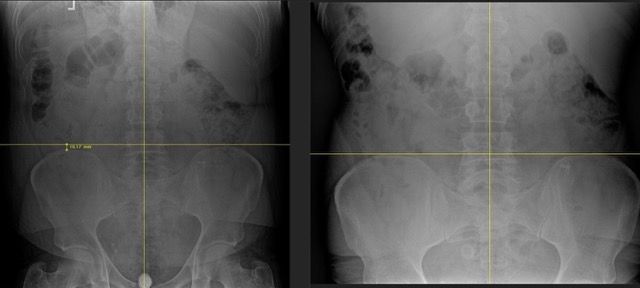

We use detailed X-rays to identify exactly what's happening in your spine. This gives us a precise starting point and allows us to track your improvement with objective measurements.

We take follow-up X-rays to show you the actual structural changes in your spine. The images don't lie – you'll see real improvement, not just temporary pain relief.

Our before and after X-rays show significant structural improvements in spinal alignment. What many doctors consider "normal degeneration" can actually be improved with the right approach.